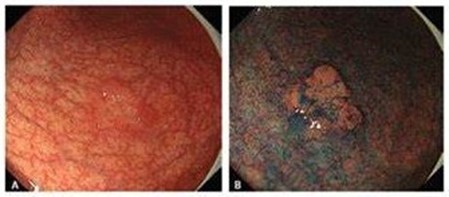

内視鏡の所見としては白色の扁平隆起と特徴とします。胃腺腫であっても基本的にはすぐにがん化をきたすことは少なく、10年単位という長い年月を経てがん化する可能性があります。

胃がんとしっかり区別する事が重要で、胃内視鏡検査での狭帯域光観察であるNBIと拡大内視鏡を用いた詳細な観察と生検による病理組織検査を行い診断していきます。胃腺腫であれば、定期的に内視鏡検査で観察をして大きさや見た目に変化がないかを確認していきます。

大きさが2cm以上になった場合、扁平の中にくぼみができた場合、白色の中に赤色を伴った場合、生検でがんに近い変化(高度異型)を認めた場合にがん化の可能性が考えられる時には、内視鏡的に切除を行う場合もあります。